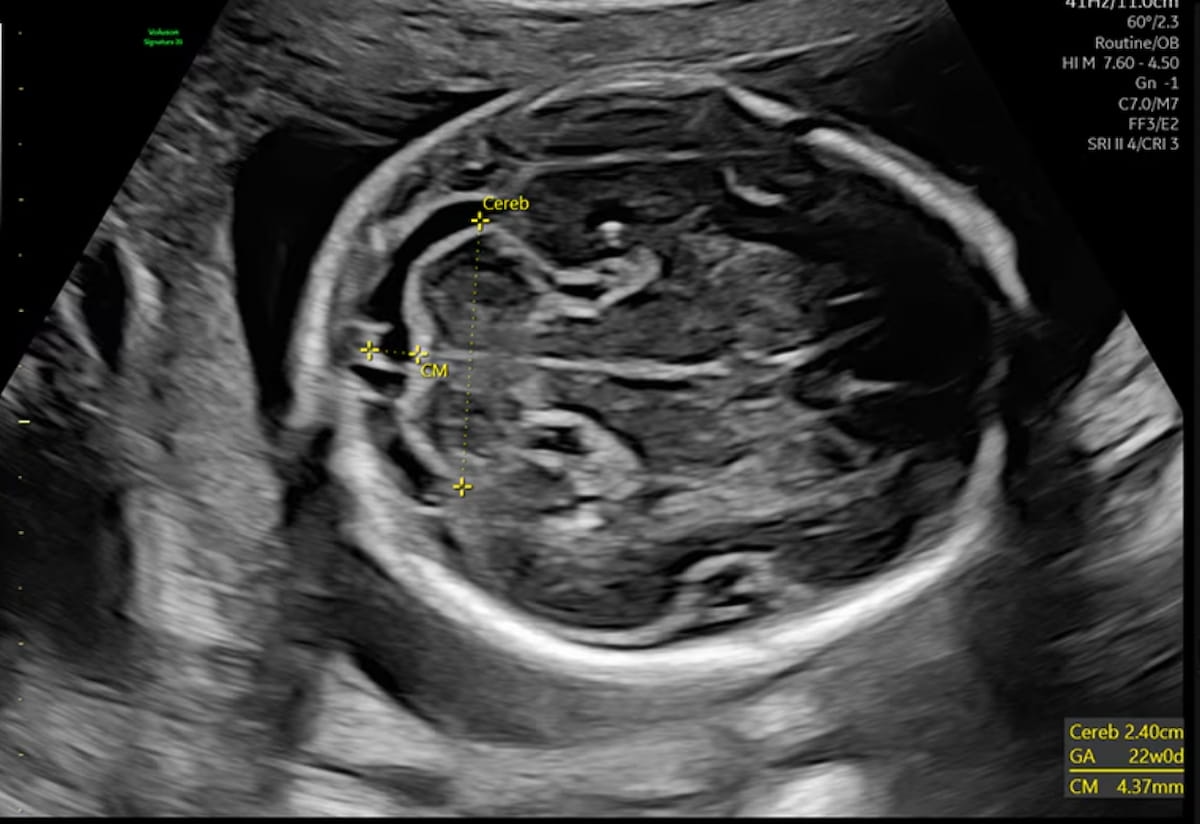

An emerging deep learning algorithm had a lower AUC and sensitivity than urological radiologists for differentiating between small renal masses on computed tomography (CT) scans but had a 21 percent higher sensitivity rate than non-urological radiologists, according to new research.